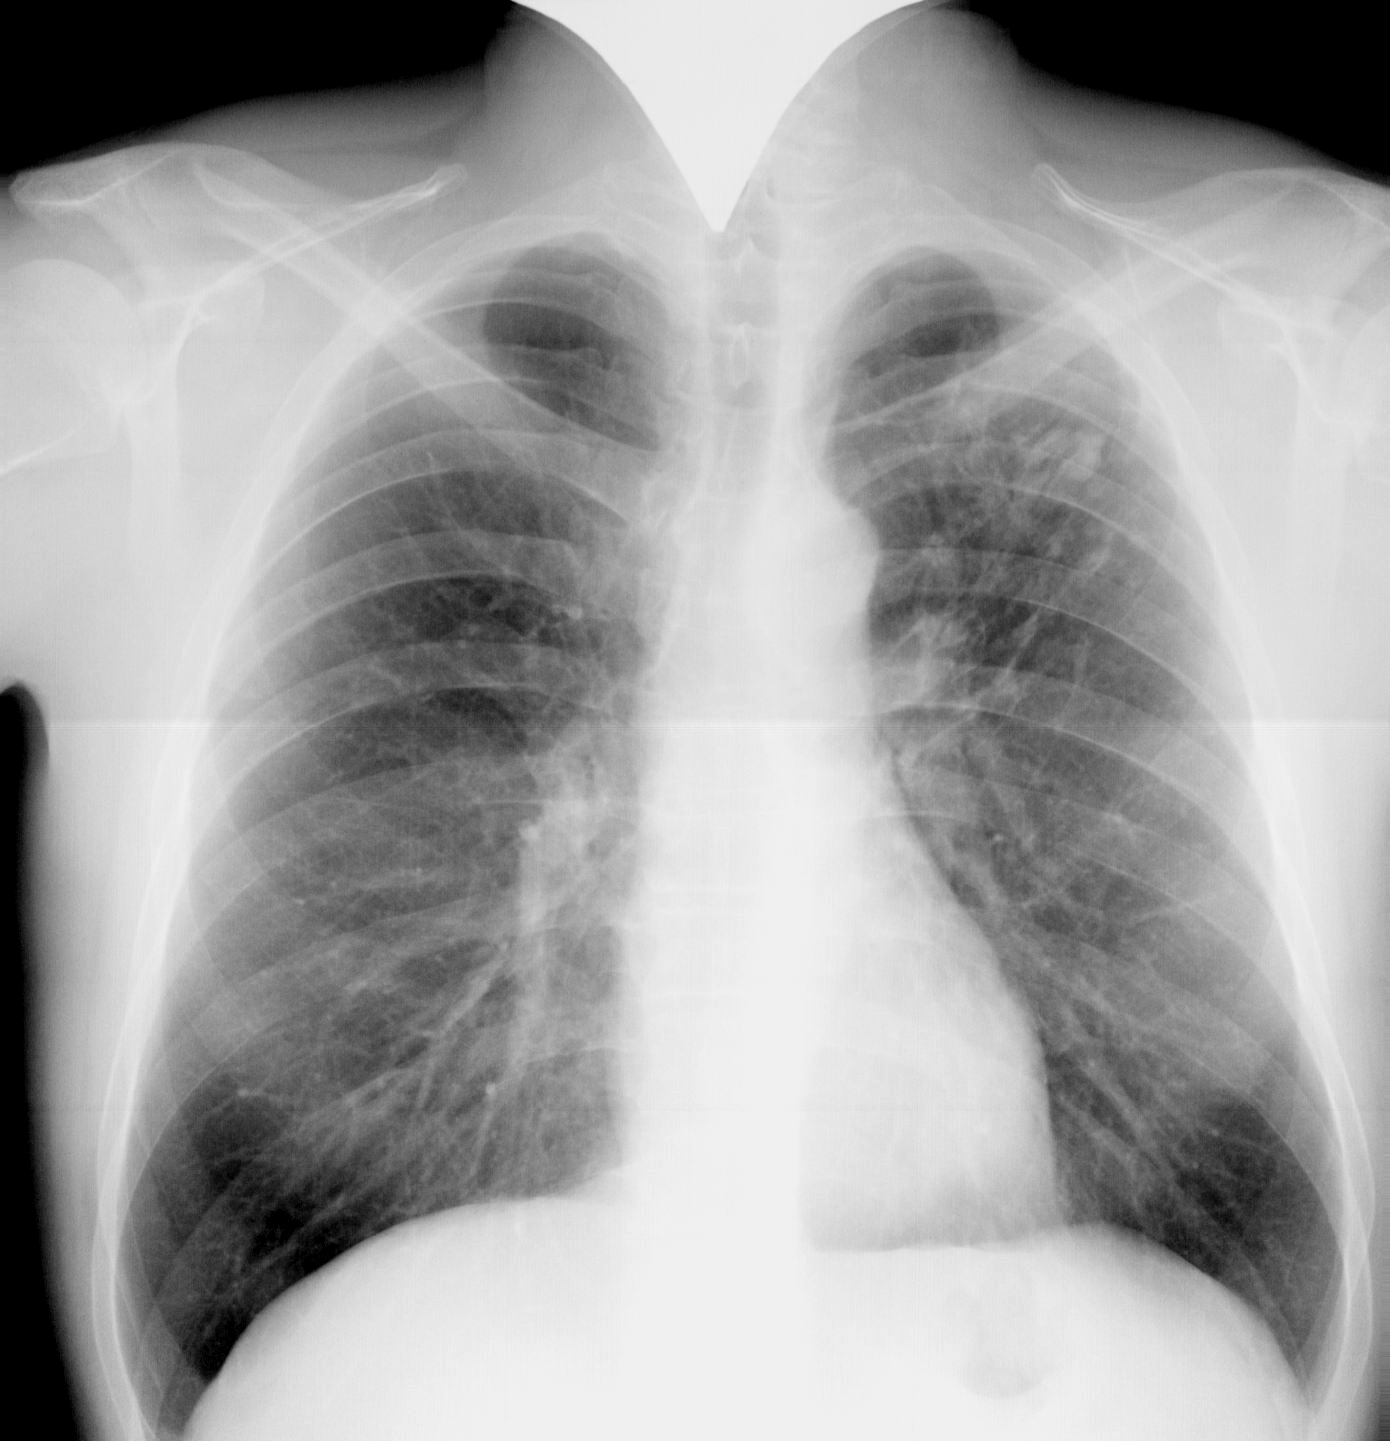

Снимок легких при туберкулезе является важным методом диагностики этого заболевания. На рентгеновских снимках можно увидеть изменения в легких, которые свойственны туберкулезу.

Фотографии снимков легких при туберкулезе

В данной статье представлены многочисленные фотографии снимков легких при туберкулезе, чтобы помочь вам понять, как выглядят изменения легких на рентгеновских снимках при этом заболевании.